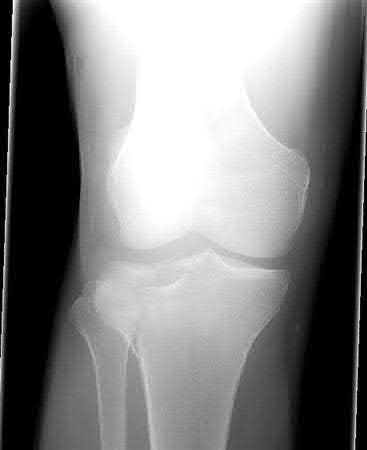

A 38-year-old male suffers the injury shown in Figure A. During operative fixation, free osteoarticular fragments are encountered and reconstruction of these pieces is attempted. Postoperatively, which of the following will have the most beneficial effect on the healing potential of the surviving chondrocytes within these reconstructed articular segments?

Figure A demonstrates a comminuted tibial plateau fracture with significant intra-articular involvement. Basic science evidence has demonstrated that post-operative gentle compressive loading may have a positive impact on articular cartilage healing; however, excessive shear loading may be detrimental.

Irrgang et al provide guidelines for rehabilitation following surgical management of articular cartilage lesions of the knee. They state that after articular cartilage repair, exercises to enhance muscle function must be done in a manner which minimizes shear loading of the joint surfaces in the area of the lesion. The authors also discuss the benefits of gentle compressive loading and motion of the joint, and its positive effects on chondrocyte nutrition.

Furthermore, they recommend a period of protected weight bearing as often being necessary, and that this should be followed by progressive loading of the joint.